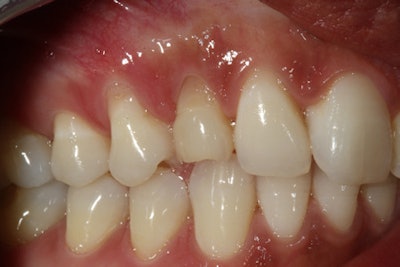

The first case illustrates how I have come to treat patients differently by using cutting-edge technologies that facilitate life-changing care. A 27-year-old woman presented for an Invisalign clear-aligner therapy consultation to discuss ways to improve her smile and occlusion. She also wanted options to replace an overretained upper right primary canine.

She had visited other dentists who planned for extraction and removal of her impacted permanent canine before any implant could be attempted. An immediate implant was not possible according to their diagnosis. Knowing our office used Galileos gave her reason to visit us for an enhanced 3D evaluation. Evaluating the scan gave me the necessary information to definitively determine that it was possible to remove the primary canine and replace it immediately without the removal of the impacted tooth.

I think everyone would agree it would be an option to remove the impaction with an invasive oral surgery procedure. That was something that did not appeal to this young woman, and she was thrilled to hear that a guided implant was a great treatment possibility. Some would consider a three-unit bridge, but I would only use this as a last resort. I also don't consider a Maryland bridge to be a viable long-term, fixed solution for this case.

The optimal treatment is to place an implant and leave the impacted canine undisturbed. Her implant experience was reflective of a flawlessly executed, guided implant placement that went exactly as planned. Her reaction to a 30-minute procedure under local anesthesia was, "That's it? I don't know why I was so nervous!" The chair time had been substantially reduced, and I even captured a smile photograph to finish off the visit.